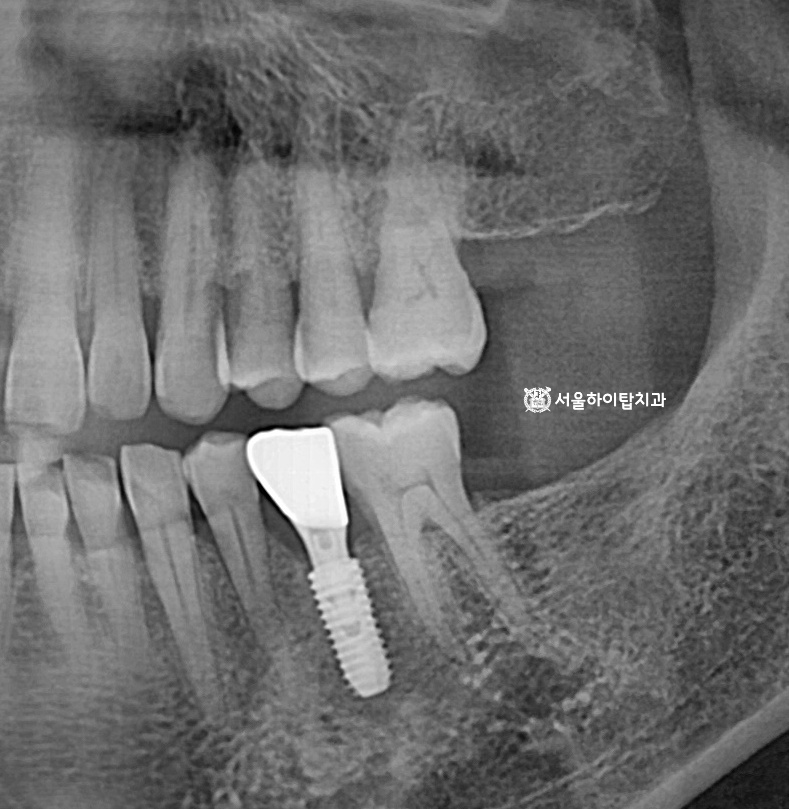

최종 결과 – 지르코니아 크라운 장착

최종 보철을 장착하기 전, 맞춤형 지대주를 체결하여

개인 구강에 맞는 보철을 장착해 주면 모든 과정은 종료됩니다.

최종적으로 지르코니아 크라운으로 장착되어

심미성과 기능이 동시에 회복되었습니다.